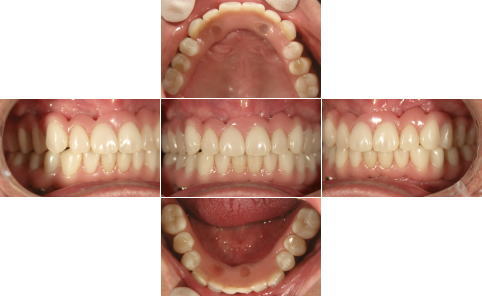

| 治療前 | 治療後 |

|---|---|

| 上顎、下顎共にグラツキの著しい歯は抜歯し、上顎はAll-on-4、下顎奥歯は通常のインプラントブリッジとしました。 | |